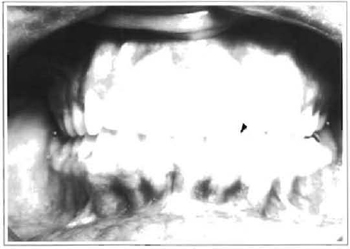

The patient began a physiotherapy program after removal of the maxillomandibular immobilization. Four months after surgery the patient presented a mandibular deviation towards the affected side, along with inadequate occlusion due to shortening of the left mandibular branch (Fig. 3). The patient was referred to an orthodontist to correct occlusion impairment. After 6 months of orthodontic treatment, proper occlusion was not obtained. (Fig.4). The x-ray at the time showed complete resorption of the condyle (Fig.5).

Fig. 4 -Right open bite after trying to solve occlusion impairment with an orthodontic method.